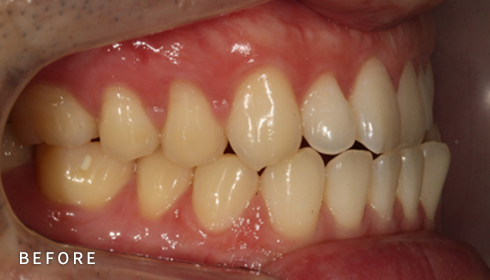

비발치 덧니 교정

덧니고민, 비발치로 교정하세요

악궁 확장, 미니 스크류, 치간 삭제 등 다양한 방법을 활용해 가능한 한

발치를 피하고, 자연스럽고 만족스러운 결과를 얻을 수 있도록

정밀하게 계획하고 진료합니다. 발치 여부가 애매한 경우,

‘레벨링 후 재평가’ 과정을 거쳐 비발치를 우선 고려합니다.